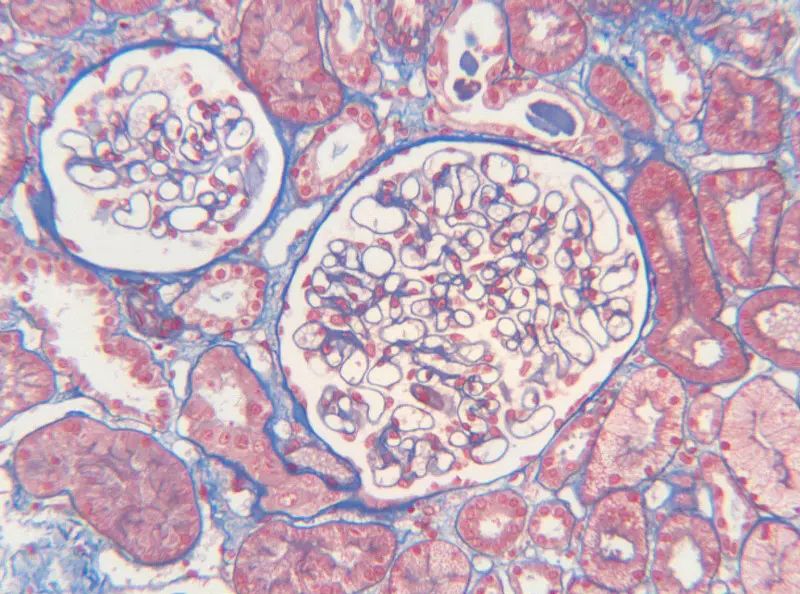

人腎組織

MASSON染色的原理主要基于陰離子染料分子的大小和組織滲透性的關(guān)系。染料分子的大小決定了其能夠滲透進(jìn)入的組織類型。小分子量的染料能夠穿透結(jié)構(gòu)致密、滲透性低的組織,而大分子量的染料則只能進(jìn)入結(jié)構(gòu)疏松、滲透性高的組織。在MASSON染色中,由于肌纖維間隙較小,麗春紅等小分子染料能夠滲透其中并染色,使其呈現(xiàn)紅色;而膠原纖維間隙較大,大分子量的苯胺藍(lán)等染料能夠進(jìn)入并染色,使其呈現(xiàn)藍(lán)色或綠色。這種染色方式使得我們能夠清晰地觀察到并區(qū)分這兩種不同的組織成分。

Step9:使用苯胺藍(lán)或光綠液染色,使膠原纖維呈現(xiàn)藍(lán)色或綠色。